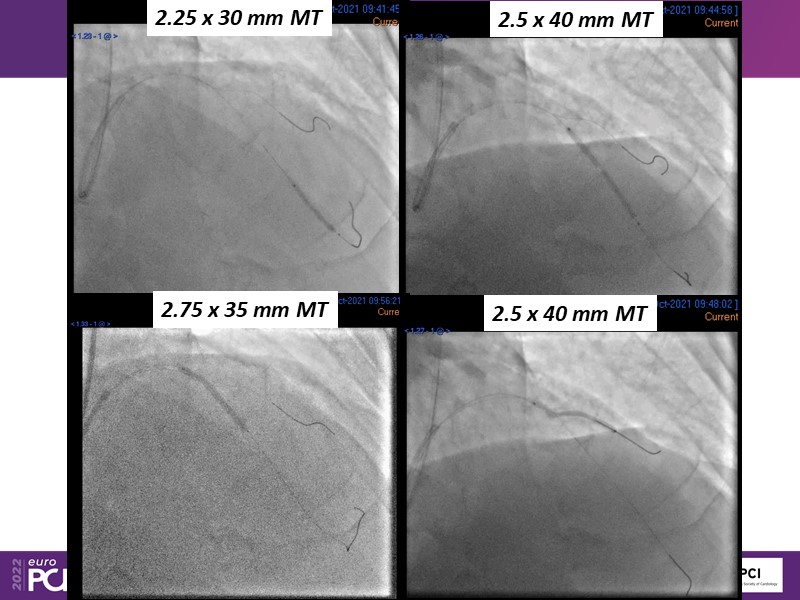

- To find out more about the application and mechanism of a sirolimus coated balloon for coronary artery disease treatment with case presentations in complex settings